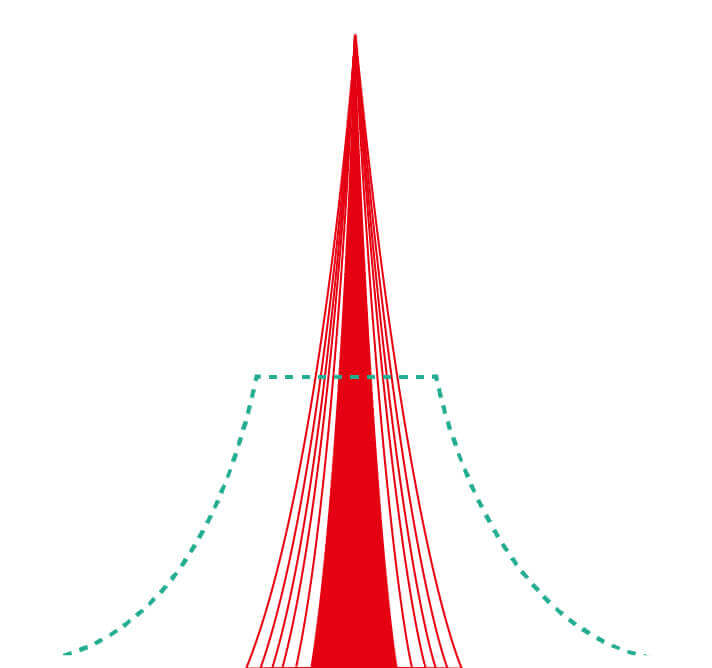

血管对比度分布光谱曲线

血管对比度分布光谱曲线

VIST光谱

VIST光谱